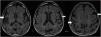

De los 54 pacientes, 33 (61,11%) presentaban atrofia global (GCA), 3 pacientes en grado2 y 30 en grado1 (fig. 1). El resto fueron clasificados con puntuación0 (sin atrofia). La edad media de estos 33 pacientes fue de 73años±8,90. Del total, 17 (31,48%) pacientes presentaron atrofia mesial (MTA): 1 con puntuación de 3, 6 con puntuación de 2 y 14 con puntuación de 1 en la escala; del total, 16 pacientes presentaban atrofia parietal en escala Koedam (1 grado 2, y 15 grado 1). En 6 pacientes encontramos atrofia frontotemporal, y en 19 pacientes encontramos lesiones vasculares con la escala Fazekas (Grado 1: 13 pacientes, Grado 2: 5 pacientes, y Grado 3: 1).